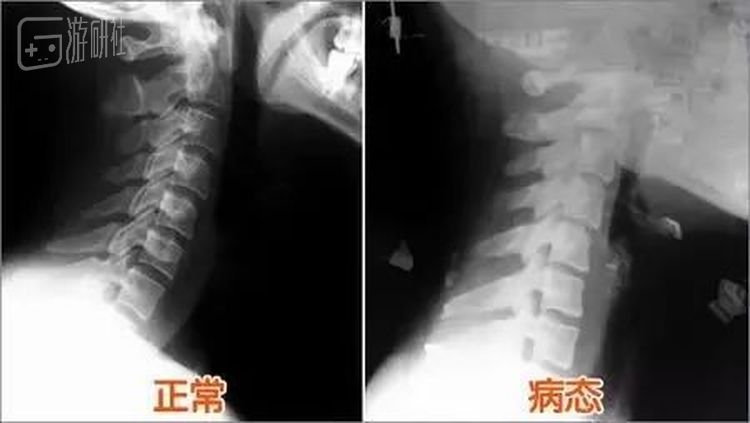

“起初只是轻微的酸痛”这种在电竞圈子里堪称职业病的症状大多数选手都有,Doinb也没把它当回事。到后来情况越来越严重,经常疼得连抬头都很困难,时不时还会伴随着头晕和手部麻痹。到了那时候他才意识到:好像问题有点大。

在家人的陪同下,他趁休假期间跑了许多家医院,最终被查出颈椎严重反曲。所有医生都在诊断建议里写上了:不宜久坐。这样的治疗方式对大多数人而言并不困难,但在Doinb眼里却几乎是一个不可能实现的操作。

除了服用药物,佩戴颈托和每周去医院进行一次治疗之外,他在生活作息和训练强度上依旧保持了以往的习惯,这让颈椎反曲治疗见效缓慢的同时,也让他的家人们感到越发不安。

“尤其是我爸妈,”他的妻子糖小幽后来跟我聊天时说道,2018年11月,古天乐颈椎移位的病情在各大媒体得到曝光,因为颈椎骨移位1cm压住神经线,导致10只手指麻痹,他被迫前往美国进行手术,在脖子里镶入了钛金属后才有所缓解。 “他们看到相关的新闻后更加担心了,生怕他以后也会变成那样。”